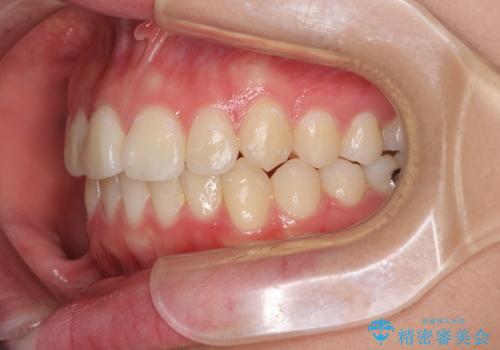

前歯のデコボコを改善 インビザライン矯正

- 口元のデコボコを気にして来院された患者様です。

前歯の捻れにより口元が閉じにくくなっていたため、歯列全体の側方への拡大と、歯と歯の間を少し削ってスペースを獲得することとしました。

ゴムかけをしっかりと行ってもらい、スッキリとした口元に仕上げることができました。